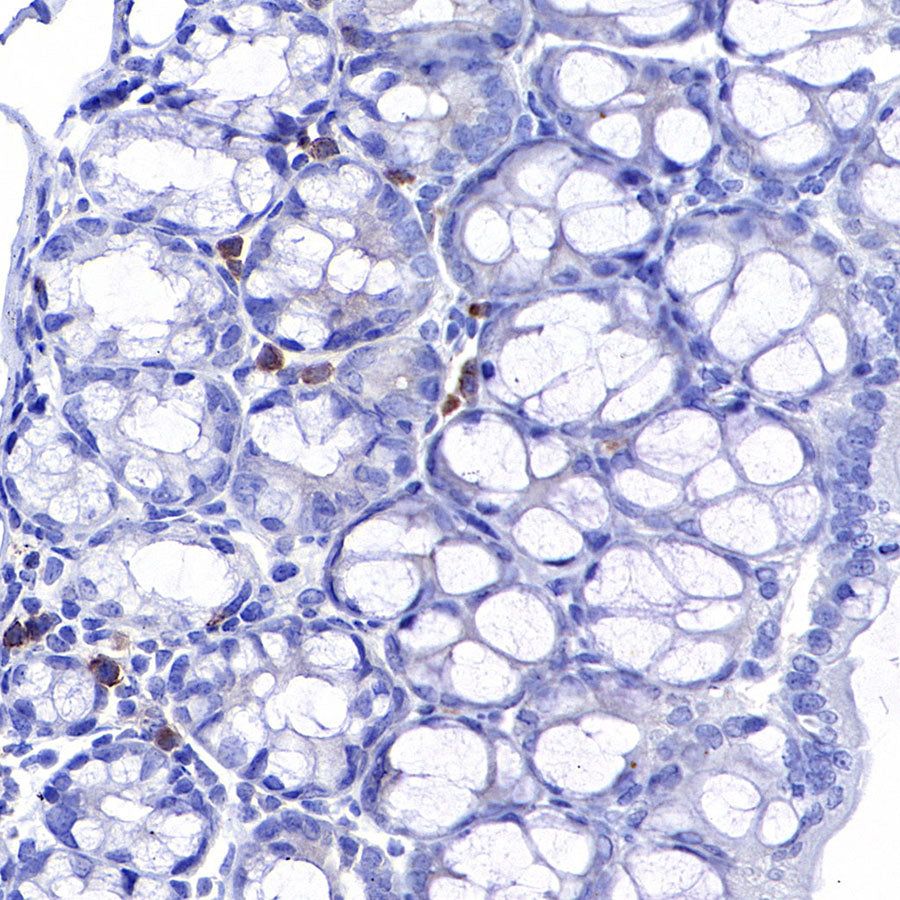

Immunohistochemistry

IHC shows positive staining in paraffin-embedded mouse spleen. Anti-CD8α antibody was used at 1/500 dilution, followed by a HRP Polymer for Mouse & Rabbit IgG (ready to use). Counterstained with hematoxylin. Heat mediated antigen retrieval with Tris/EDTA buffer pH9.0 was performed before commencing with IHC staining protocol.

IHC shows positive staining in paraffin-embedded mouse colon. Anti-CD8α antibody was used at 1/500 dilution, followed by a HRP Polymer for Mouse & Rabbit IgG (ready to use). Counterstained with hematoxylin. Heat mediated antigen retrieval with Tris/EDTA buffer pH9.0 was performed before commencing with IHC staining protocol.